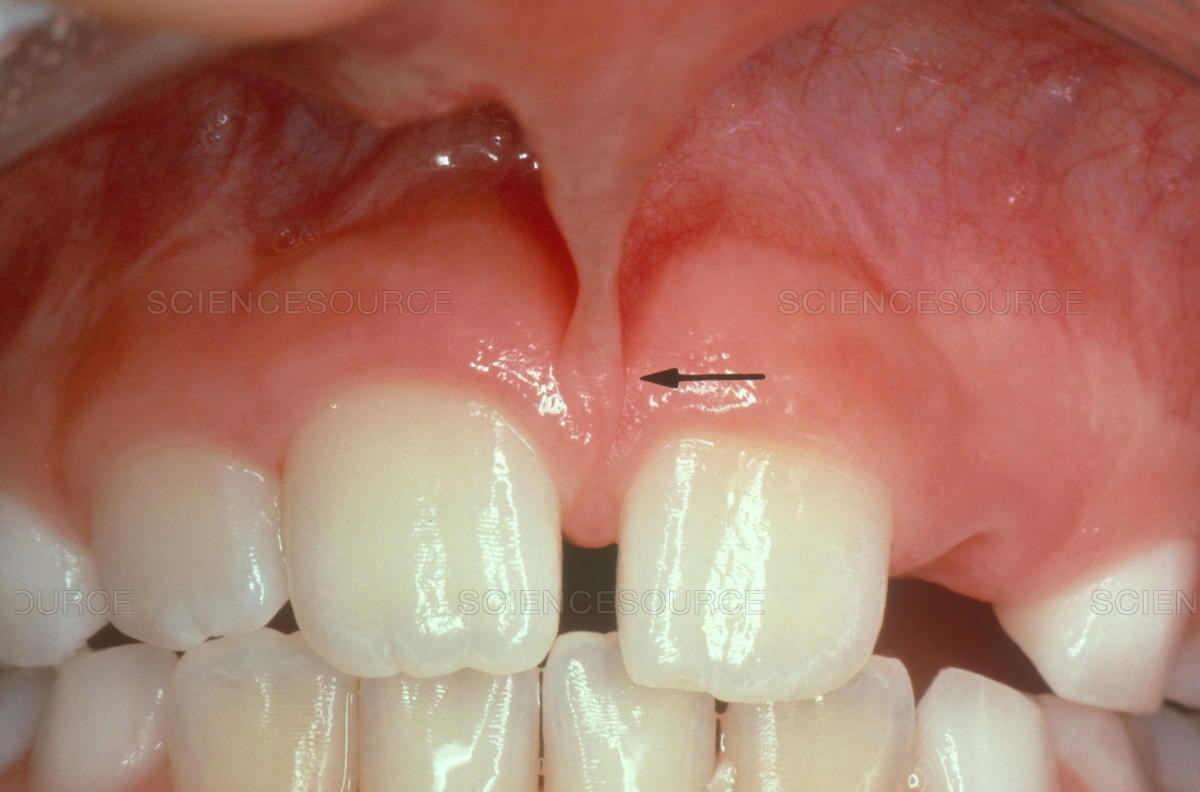

In our mouth, most people have two groups of tissue called frenums found in and around the gums and teeth. It is a piece of really soft tissue that appears as a thin line between the gums and lips. You can find it on the top and the bottom of your oral cavity. There’s also a frenum that extends along the bottom of the tongue and connects to the bottom of the mouth just behind the teeth. Different people have different frenums. It can vary in length and thickness.

Labial frenum – This type of frenum is placed in the front of your mouth between the upper lip and gum. His counterpart is positioned between the lower gum and the lower lip. If there is an issue with this type of frenum, it can change the way your teeth grow in and can influence your dental health. Particularly it can pull your gums away from a tooth revealing the root.

· disruption of the healthy growth of your upper two front teeth, which may cause a gap

· the gap formed between front teeth